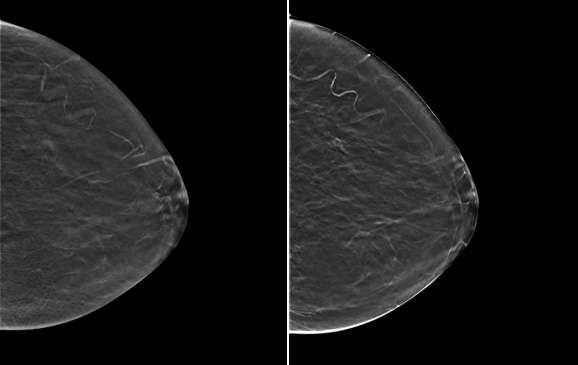

Traditionally, 2D mammograms have been performed, which offer a two-dimensional image of the breast. Screening mammograms are usually performed in two standard views, the craniocaudal (CC) and the mediolateral oblique (MLO) views. Additional diagnostic views including spot compression or variant angles may also be obtained. The differential attenuation characteristics of tissue allow for the identification of masses, calcifications, and other findings. For example, mammography can demonstrate suspicious microcalcifications that may otherwise not be palpable. Both screen film and, more recently, digital mammography formats have utilized 2D imaging.

Digital breast tomosynthesis (DBT), colloquially known as 3D mammography, is a newer technology that was approved by the FDA in 2011. DBT acquires multiple mammographic projections serially along an arc and reconstructs this data via post-processing techniques into thin slice images to create a quasi-three-dimensional assessment of the breast. These reconstructed images result in partial blurring of features outside the selected plane. The multiple thin images allow radiologists to scroll through each image separately and attenuates the pitfall of superimposed breast tissue in a conventional 2D mammogram.